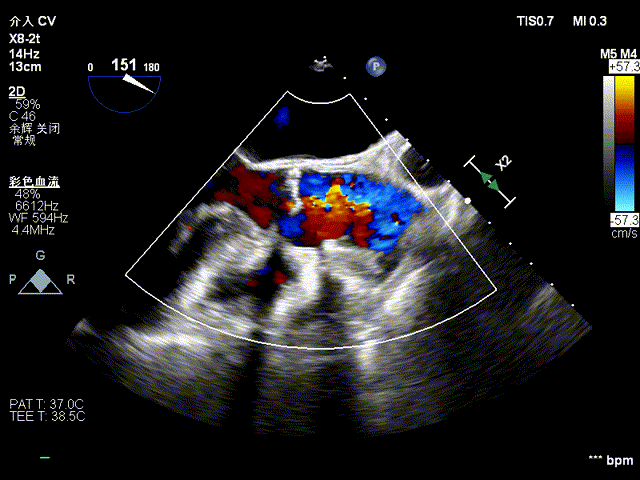

复查造影示瓣膜位置,功能,形态良好,无冠脉堵塞,术中TEE证实主动脉瓣生物瓣位置及功能正常,未见瓣周漏,仅微量反流。

术后食道超声

术后心脏超声示

经心尖主动脉瓣生物瓣置换术后,生物瓣功能未见明显异常,微量心包积液。LVEF:68%。

主动脉瓣位生物瓣,瓣架固定,瓣叶启闭尚可,主动脉瓣位生物瓣前向峰值流速约1.8m/s,平均跨瓣压差约8mmHg,舒张期少量周反流。